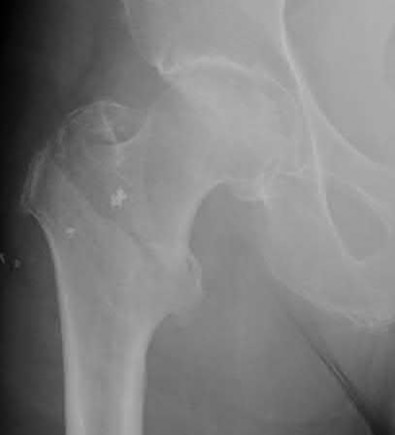

Question 1:

A 12-year-old obese boy presents with vague left thigh and knee pain. He is diagnosed with a Slipped Capital Femoral Epiphysis (SCFE) as seen in similar clinical scenarios. During percutaneous in-situ fixation, unrecognized penetration of the guide wire into the hip joint occurs. What is the most likely specific complication resulting from this technical error?

Correct Answer: Chondrolysis

Explanation:

Chondrolysis is a severe complication of SCFE characterized by rapid destruction of the articular cartilage. While it can occur idiopathically, its most established iatrogenic cause is unrecognized intra-articular hardware penetration. The 'approach-withdraw' fluoroscopic technique is required during pinning to assure pins are entirely intraosseous. Avascular necrosis (AVN) is usually due to damage to the epiphyseal blood supply (retinacular vessels) secondary to the initial displacement, forceful closed reduction, or posterosuperior pin placement.